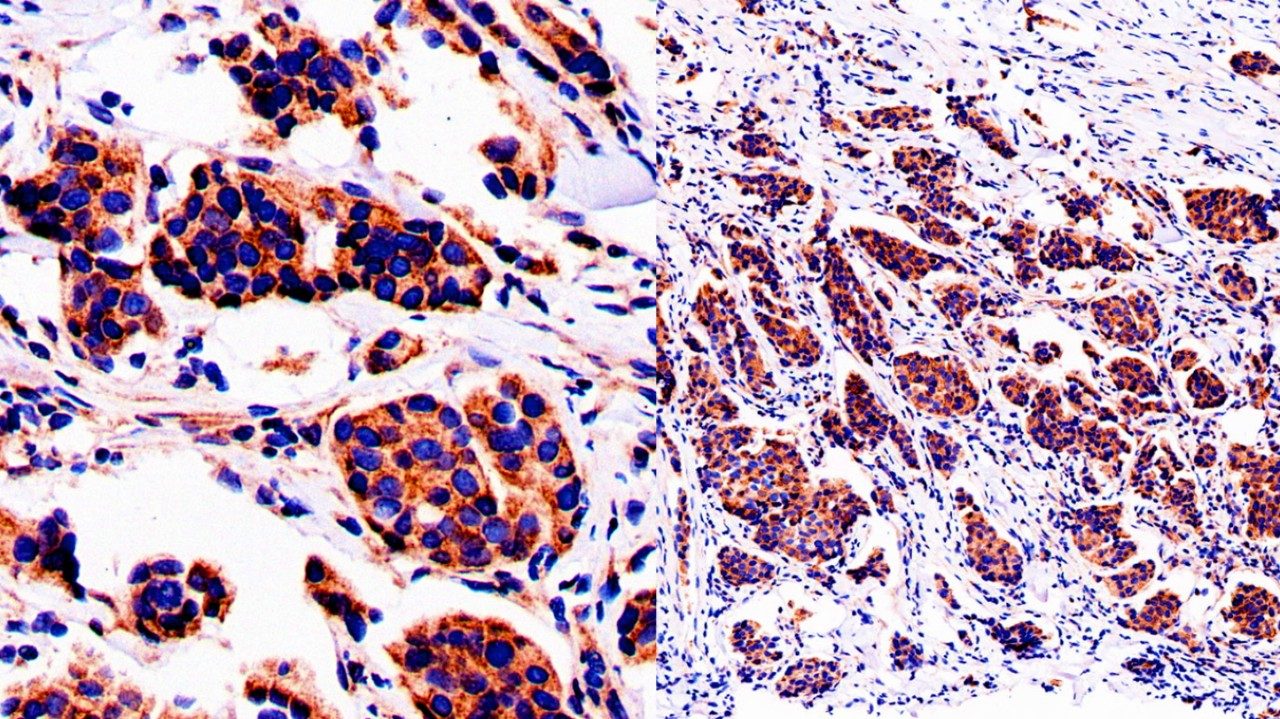

After conducting additional tests, Iheme and the rest of my care team — including breast surgical oncologist Dr. Taiwo Adesoye and breast radiation oncologist Dr. Melissa Mitchell — recommended a Phase 2 clinical trial with a novel HER2 targeted therapy drug in combination with endocrine therapy. It involved a new bispecific antibody called zanidatamab that was already being used successfully to treat HER2+ metastatic breast cancer, bile duct cancer and other gastric cancers. The preliminary results of the Phase 2 clinical trial were promising. So, I agreed to take part.

Breast medical oncologist Dr. Vicente Valero, who was leading the clinical trial, agreed. He called it “a very robust response.”

By the time I finished the clinical trial, my breast was totally clear, so I could have a lumpectomy instead of a mastectomy. The pathology report showed I’d had a complete pathological response. There was no evidence of residual cancer in my breast or lymph nodes.